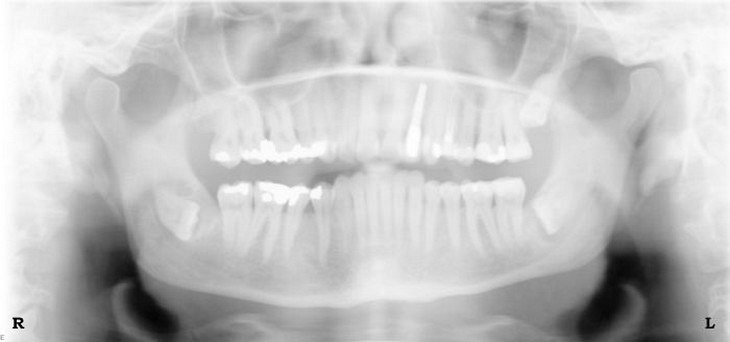

At Hobsonville Point Dental we have both intraorol digital radiography and extraoral full mouth digital x-rays. With intraoral digital x-rays, a sensor or digital plate is inserted into your mouth to capture an image of your teeth. For extraoral full mouth digital x-rays, to capture a complete image of your jaw, patients instead stand in a scanning x-ray – orthopantomogram (panorex). It’s a quick, convenient and very efficient process to almost immediately capture an image of your oral health.

Here are examples of digital dental radiography